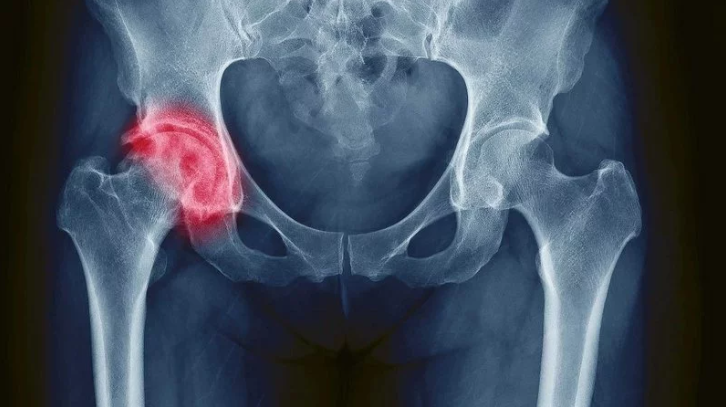

دررفتگی مادرزادی لگن زمانی رخ می‌دهد که سر گرد استخوان ران به‌درستی داخل حفره لگن (استابولوم) قرار نگرفته باشد. این مشکل ممکن است از لحظه تولد وجود داشته باشد یا در هفته‌های اول زندگی مشخص شود. در برخی کودکان سر استخوان ران کاملاً بیرون از حفره است و در برخی دیگر فقط شل و ناپایدار است. این بیماری در دختران حدود ۷ برابر بیشتر از پسران دیده می‌شود و معمولاً لگن چپ بیشتر درگیر می‌شود. اگر درمان نشود، با بزرگ شدن کودک، کوتاه شدن پا و درد شدید ایجاد می‌کند. تشخیص و درمان به‌موقع باعث می‌شود کودک زندگی کاملاً طبیعی داشته باشد.

تمام نوزادان باید بلافاصله پس از تولد و در ماه‌های بعدی توسط متخصص ارتوپدی کودکان معاینه شوند. تا ۴–۶ ماهگی سونوگرافی بهترین روش تشخیص است چون هنوز غضروف‌ها استخوانی نشده‌اند. بعد از ۴–۶ ماهگی از عکس رادیوگرافی ساده استفاده می‌شود. در موارد مشکوک،MRI یا CT هم به کار می‌رود. زاویه استابولوم و موقعیت سر استخوان ران در عکس‌ها بررسی می‌شود. تشخیص زودرس باعث می‌شود بیش از ۹۵ درصد کودکان با روش‌های ساده درمان شوند.